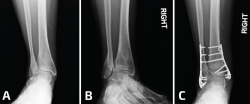

Se puede recurrir a la osteotomía de la tibia para corregir la deformidad en valgo del pilón. Esto se puede realizar mediante una cuña de sustracción interna o una cuña de adición externa de la tibia (Figura 6). En este caso, la consolidación viciosa oblicua del peroné facilitará la osteotomía oblicua del mismo para lograr una buena elongación y en este caso no se utilizaría injerto óseo(11).

Figura 6. En un caso donde el plafón tibial se encuentra en valgo, solo elongar el peroné no será suficiente. Observen el pie plano como resultado del tobillo y el retropié en valgo (A, B). Se realizaron conjuntamente una elongación del peroné, una osteotomía en cuña de cierre con base medial de la tibia y una osteotomía medializadora del calcáneo. Observen una mejoría en la alineación, pero la persistencia de un leve valgo de tobillo (C, D).

Otra variante de una consolidación viciosa del peroné se asocia con la compresión del pilón externo y la inclinación en valgo de la mortaja del tobillo. Como se describió más arriba, estos casos deben tratarse mediante osteotomía del peroné, además de una osteotomía en cuña de sustracción de la cara interna de la tibia para la realineación del tobillo (Figuras 8 y 9).

Figura 9. Las consolidaciones viciosas o pseudoartrosis del peroné pueden producirse en el contexto de una fractura de estrés. En este paciente, una fractura por estrés tras una triple artrodesis indica una deformidad en valgo (A, B). A pesar de elongar 1 cm el peroné, se debe realizar una osteotomía de cierre lateral de la tibia distal (C, D).